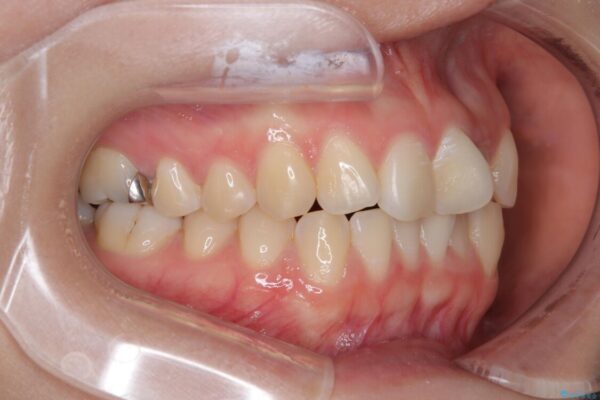

治療前

• 前歯のねじれ・ガタガタを10か月で改善!20代女性の矯正治療|クリアブラケットでむし歯になりにくい歯並びへ改善 治療前画像

診察の結果、上下の前歯部に**叢生(そうせい/歯のガタガタ・重なり)**が認められました。

特に上の前歯にはねじれや重なりがあり、審美的にも清掃性にも影響している状態でした。